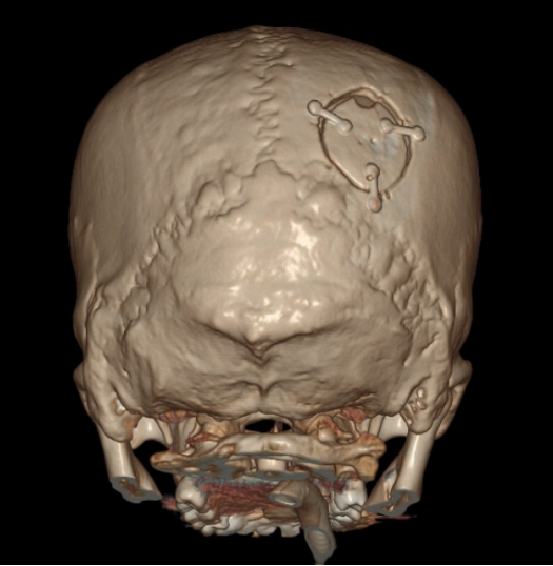

穿刺位置:枕骨粗隆上8.5cm,中线旁开3.5cm

穿刺深度:6.3cm

术前CT

血肿内疑似有血管畸形